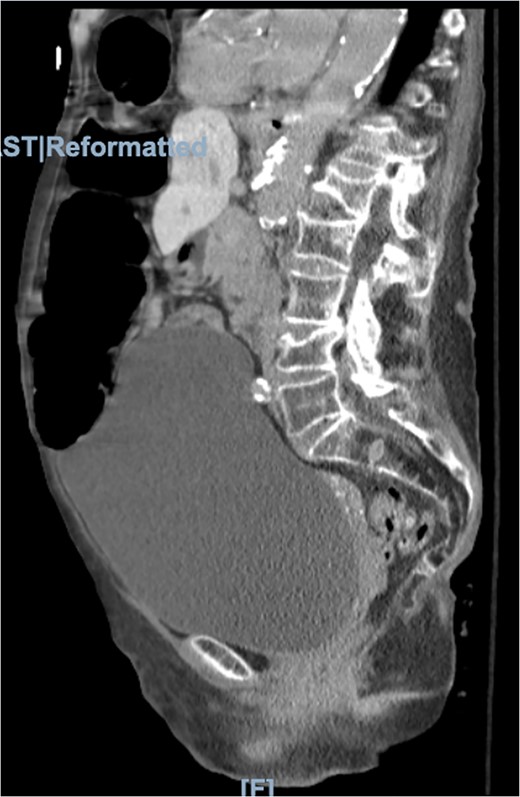

Physical examination was significant for right upper quadrant and epigastric tenderness with a mildly distended abdomen. On admission, the patient had a leukocytosis of 16.2. Imaging included computed tomography (CT) of the abdomen and pelvis showing the obstruction of the colon suspected because of a loop of colon herniated into the lower anterior chest, between the lower aspect of the sternum and the left heart border with mild mass-effect on the heart (Figs 2 and 3).

Morgagni hernia seen on CT abdomen and pelvis with contrast (sagittal view).